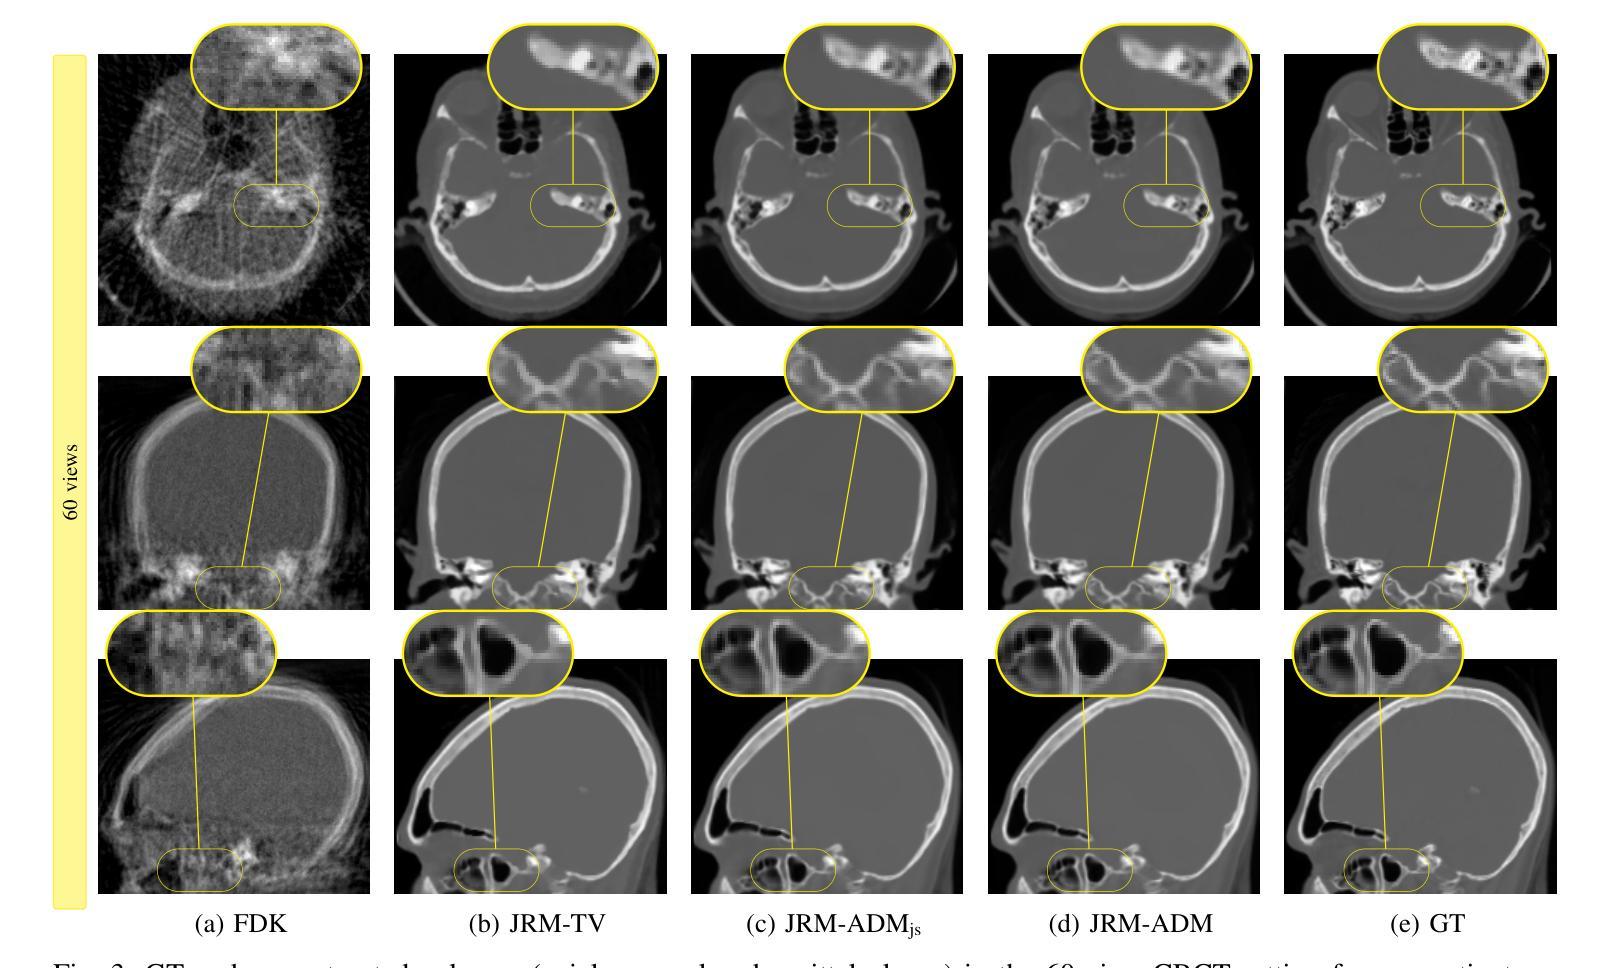

Adaptive Diffusion Models for Sparse-View Motion-Corrected Head Cone-beam CT

Cone-beam computed tomography (CBCT) is an imaging modality widely used in head and neck diagnostics due to its accessibility and lower radiation dose. However, its relatively long acquisition times make it susceptible to patient motion, especially under sparse-view settings used to reduce dose, which can result in severe image artifacts. In this work, we propose a novel framework, joint reconstruction and motion estimation (JRM) with adaptive diffusion model (ADM), that simultaneously addresses motion compensation and sparse-view reconstruction in head CBCT. Leveraging recent advances in diffusion-based generative models, our method integrates a wavelet-domain diffusion prior into an iterative reconstruction pipeline to guide the solution toward anatomically plausible volumes while estimating rigid motion parameters in a blind fashion. We evaluate our method on simulated motion-affected CBCT data derived from real clinical computed tomography (CT) volumes. Experimental results demonstrate that JRM- ADM achieves consistent quantitative improvements over both traditional and learning-based baselines. In highly undersampled cases, JRM-ADM improves peak signal-to-noise ratio (PSNR) by more than 4 dB and structural similarity index measure (SSIM) by 0.10 compared to baseline the motion-corrected (MC) reconstruction method. These results highlight the potential of our approach to enable motion-robust and low-dose CBCT imaging, paving the way for improved clinical viability. The project page is available at https://antoinedepaepe.github.io/jrm-adm-io/.

锥束计算机断层扫描(CBCT)是一种在头部和颈部诊断中广泛使用的成像方式,因其可及性和较低的辐射剂量而受到欢迎。然而,其相对较长的采集时间使其容易受到患者运动的影响,特别是在用于减少剂量的稀疏视图设置下,可能导致严重的图像伪影。在这项工作中,我们提出了一种新型框架,即联合重建和动态估计(JRM)与自适应扩散模型(ADM),该框架可以同时解决头部CBCT中的运动补偿和稀疏视图重建问题。利用基于扩散的生成模型的最新进展,我们的方法将小波域扩散先验知识集成到迭代重建流程中,以向解剖上合理的体积引导解决方案,同时以盲态估计刚体运动参数。我们在从真实的临床计算机断层扫描(CT)体积派生的模拟运动影响CBCT数据上评估了我们的方法。实验结果表明,与基于传统和学习的基线相比,JRM-ADM持续实现了定量改进。在高度欠采样的情况下,与基于运动的校正(MC)重建方法相比,JRM-ADM的峰值信噪比(PSNR)提高了超过4分贝,结构相似性指数度量(SSIM)提高了0.10。这些结果突出了我们的方法在实现稳健运动和低剂量CBCT成像方面的潜力,为改善临床可行性铺平了道路。项目页面可在[https://antoinedepaepe.github.io/jrm-adm-io/]上找到。

Summary

本文提出了一个联合重建和运动估计(JRM)与自适应扩散模型(ADM)的新框架,用于解决头部锥形束计算机断层扫描(CBCT)中的运动补偿和稀疏视图重建问题。该框架利用基于扩散的生成模型的最新进展,将小波域扩散先验集成到迭代重建管道中,以引导解决方案朝向解剖上合理的体积,同时以盲的方式估计刚体运动参数。实验结果表明,JRM-ADM相较于传统和基于学习的方法在模拟运动影响的CBCT数据上实现了持续的定量改进。在高度欠采样的情况下,与基于运动的校正(MC)重建方法相比,JRM-ADM的峰值信噪比(PSNR)提高了超过4分贝,结构相似性指数度量(SSIM)提高了0.1。这为运动鲁棒和低剂量CBCT成像的实现提供了潜力,为提高临床可行性铺平了道路。

Key Takeaways

1. CBCT在头颈诊断中广泛应用,但其较长的采集时间易受到患者运动的影响,导致图像出现严重伪影。

2. 提出了一个名为JRM-ADM的新框架,同时解决运动补偿和稀疏视图重建问题。

3. 利用扩散模型生成小波域扩散先验,将其集成到迭代重建管道中。

4. JRM-ADM方法能引导解决方案向解剖上合理的体积发展,并盲估刚体运动参数。

5. 实验结果表明,JRM-ADM在模拟运动影响的CBCT数据上表现优于传统和基于学习的方法。

6. 在高度欠采样情况下,JRM-ADM的PSNR和SSIM指标相较于运动校正方法有明显提升。